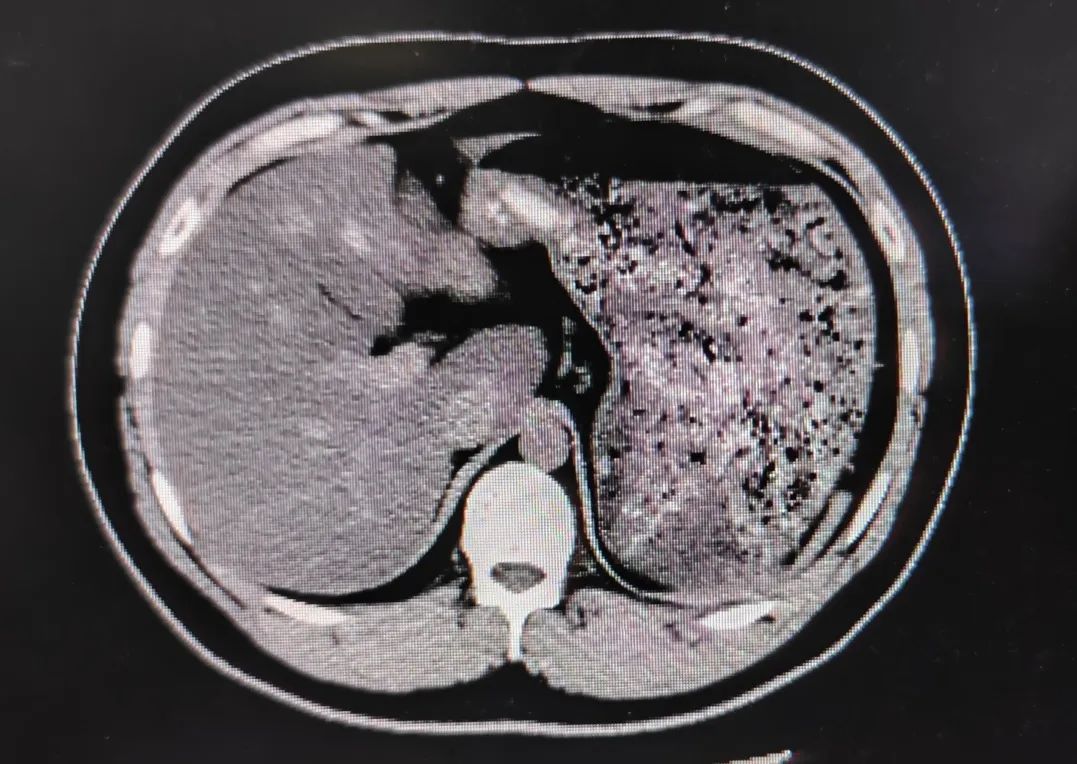

患者不喝水或少喝水,没有充盈的胃肠道管壁很厚,容易遗漏胃肠道本身的器质性病变。

没有充盈的胃肠道显示的软组织密度和真正可能存在的软组织密度的病灶难以鉴别。